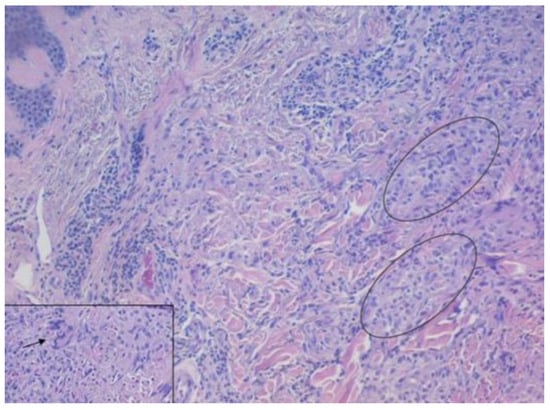

| First Author/Year | Age/Sex | Country | Duration | Immunosuppression/Cause | Site | Culture TB/Mantoux | Histology | Response to Therapy |

|---|---|---|---|---|---|---|---|---|

| Damevska K/2013 [4] | 65, F | Republic of North Macedonia | 60 y | Immunocompetent/Ν.A. | Bilateral upper limbs and right lower limb | Negative/(+) | Granulomatous inflamma-tion in the dermis, with small foci of caseation necrosis | Damevska K/2013 [4] |

| Rahman MH/2020 [5] | 12, M | Bangladesh | 2 y | Immunocompetent/bare-footed child | Bilateral extremities | N.A./(+) 17 mm | Hypertrophy of the epidermis and mid-dermalgranuloma with Langhans giant cells | At 6 months, complete resolution of the lesions |

| Rajan J/2011 [6] | 17, M | India | 2 y | Immunocompetent/cattleherd | Left foot | N.A./(+) 17 mm | Hypertrophy of the epidermis and mid-dermal granulomata with Langhans giant cells | At 6 months, all the lesions were completely resolved |

| Vora RV/2016 [7] | 60, F | India | 12 y | Immunocompetent/a thorn prick over her right big toe | Right lower limb | N.A./(−) | Hyperkeratosis, acanthosis of the epidermis. Below the epidermis, multiple granulomas, comprised epithelioid cells with Langhans | At 3 months, improvement of the lesions |

| Sudarshan R/2016 [8] | 69, F | India | 14 y | Immunocompetent/farmer handling cattle occasionally | Right upperlimb, lower limbs, face and nape | Negative/(−) | Hyperplasia, hyperkeratosis and hypergranulosis. Dermis epithelioid cell granulomas with many Langhans giant cells and lymphoplasmacytic infiltrate | Incomplete response after 1 year of therapy |

| Chahar M/2015 [9] | 48, M | India | 15 y | Immunocompetent/walking barefoot | Bilateral buttocks and feet | Negative/(+) | Hyperkeratosis, acanthosis, papillomatosis. Upper dermis mononuclear infiltrate and mid-dermis. Epithelioid cell granulomas comprising Langhans giant cells | At 6 months, complete resolution of the lesions |

| Verma R/2014 [10] | 30, M | India | 3 y | Immunocompetent/farmer | Right lower limb | Negative/(+) | Pseudoepitheliomatous hyperplasia with irregular acanthosis. Dermis epithelioid cell granulomas with Langhans giant cells and neutrophilic microabscesses | At 6 months, resolution of the lesions |

| Rasineni N/2014 [11] | 42, F | India | 4 m | N.A./N.A. | Left sole and left index finger | Negative/(+) 20 mm | Hyperkeratosis along with numerous lymphocytes, epithelioid cells, and Langhans giant cells in the dermis | At 5 months, complete clearance |

| Manjumeena D/2018 [12] | 52, F | India | 20 y | Immunocompetent/trauma while cutting wood | Left leg and foot | Negative/(+) | Hyperkeratosis, acanthosis, papillomatosis, granulomas composed of lymphocytes, neutrophils, giant cells with central caseous necrosis | At 6 months, regression of the lesions |

| Sehgal VN/2017 [13] | 78, M | India | 1 y | N.A/N.A | upper and lower extremities | N.A./(−) | Epithelial hyperplasia, papillomatosis, and perivascular inflammation in dermis. Epithelioid cell granuloma | At 6 months, complete regression of the lesions |

| Rani S/2020 [14] | 29, M | India | 2 y | Immunocompetent/farmer | Heel, antero-posterior and medial side of leg | Negative/(+) 20 mm | Hyperkeratosis, acanthosis, dermal infiltration with epithelioid cell granulomas with Langhans giant cells and occasional central necrosis | At 5 months, improvement of the lesions |

| Prasad PVS/2002 [15] | 35, M | India | 2 y | Immunocompetent | Left hand and left foot | Negative/(−) | Hyperkeratosis, acanthosis, and mid-dermal tuberculoid granulomas | - |

| Padmaprasad MK/2013 [16] | 49, F | India | 2 y | Immunocompetent/butcher | Right shoulder, right breast, lower limbs and buttocks | Negative/(+) 22 mm | Pseudoepitheliomatous hyperplasia, dense infiltration of plasma cells and giant cells, and caseation necrosis | N.A. |